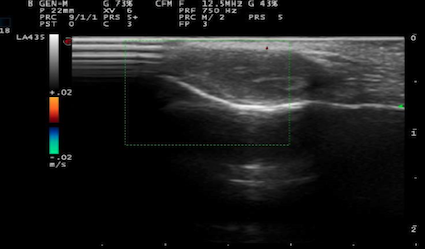

Una bambina di due anni giunge alla nostra osservazione per la presenza da circa 3 mesi di una tumefazione asintomatica, non dolente, in sede retroauricolare (Figura 1). La bambina si presenta in buone condizioni generali, la lesione è di consistenza aumentata, dura, sottocutanea, ferma che sembra adesa ai piani profondi con cute sovrastante integra. Viene eseguito l’ecografia, che mostra una piccola area ipoecogena di circa 10,5 mm x 5,5 mm, ben delimitata, osso integro, non vascolarizzata all’ecoDoppler (Figura 2).

Non è necessario nessun trattamento perché il granuloma anulare profondo si riassorbe spontaneamente nell’arco di mesi o qualche anno. Se l’età è tipica, con sede e aspetto ecografico congruenti, si può evitare la biopsia e seguire l’evoluzione nel tempo.